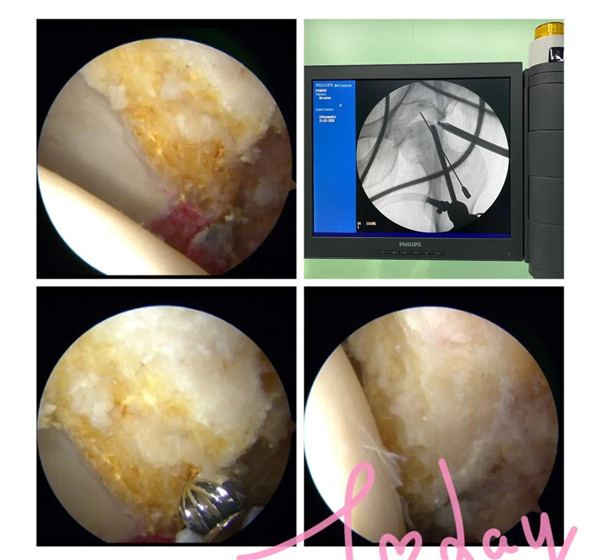

2月21日,經(jīng)過周密的術(shù)前準(zhǔn)備,羅軍帶領(lǐng)手術(shù)團(tuán)隊(duì)為余大伯開展髖關(guān)節(jié)鏡手術(shù)。術(shù)中,完成了髖關(guān)節(jié)鏡下探查清理、頭頸成形術(shù),髖關(guān)節(jié)鏡下清理術(shù),順利去除了髖關(guān)節(jié)撞擊征及盂唇破裂等病灶,并聯(lián)合運(yùn)用富血小板血漿技術(shù)治療患者的股骨頭壞死。

(術(shù)中磨去增生的骨贅)

針對(duì)股骨頭壞死早期,富血小板血漿療法(PRP)是一項(xiàng)十分成熟的治療技術(shù),近10年來在歐美被廣泛應(yīng)用,尤其在運(yùn)動(dòng)員受傷時(shí)使用,很多大家所熟知的NBA籃球運(yùn)動(dòng)員都曾接受過這項(xiàng)技術(shù)的治療。配合髖關(guān)節(jié)鏡技術(shù)治療更加精準(zhǔn)。該療法只需抽取患者20毫升靜脈血,離心和分離出富血小板血漿后注射入患者的股骨頭壞死區(qū)域,達(dá)到修復(fù)損壞的關(guān)節(jié)軟骨,改善股骨頭缺血壞死,進(jìn)而保護(hù)關(guān)節(jié)、緩解疼痛的目的。

(術(shù)中去除壞死的組織并在壞死區(qū)域植入富血小板血漿)